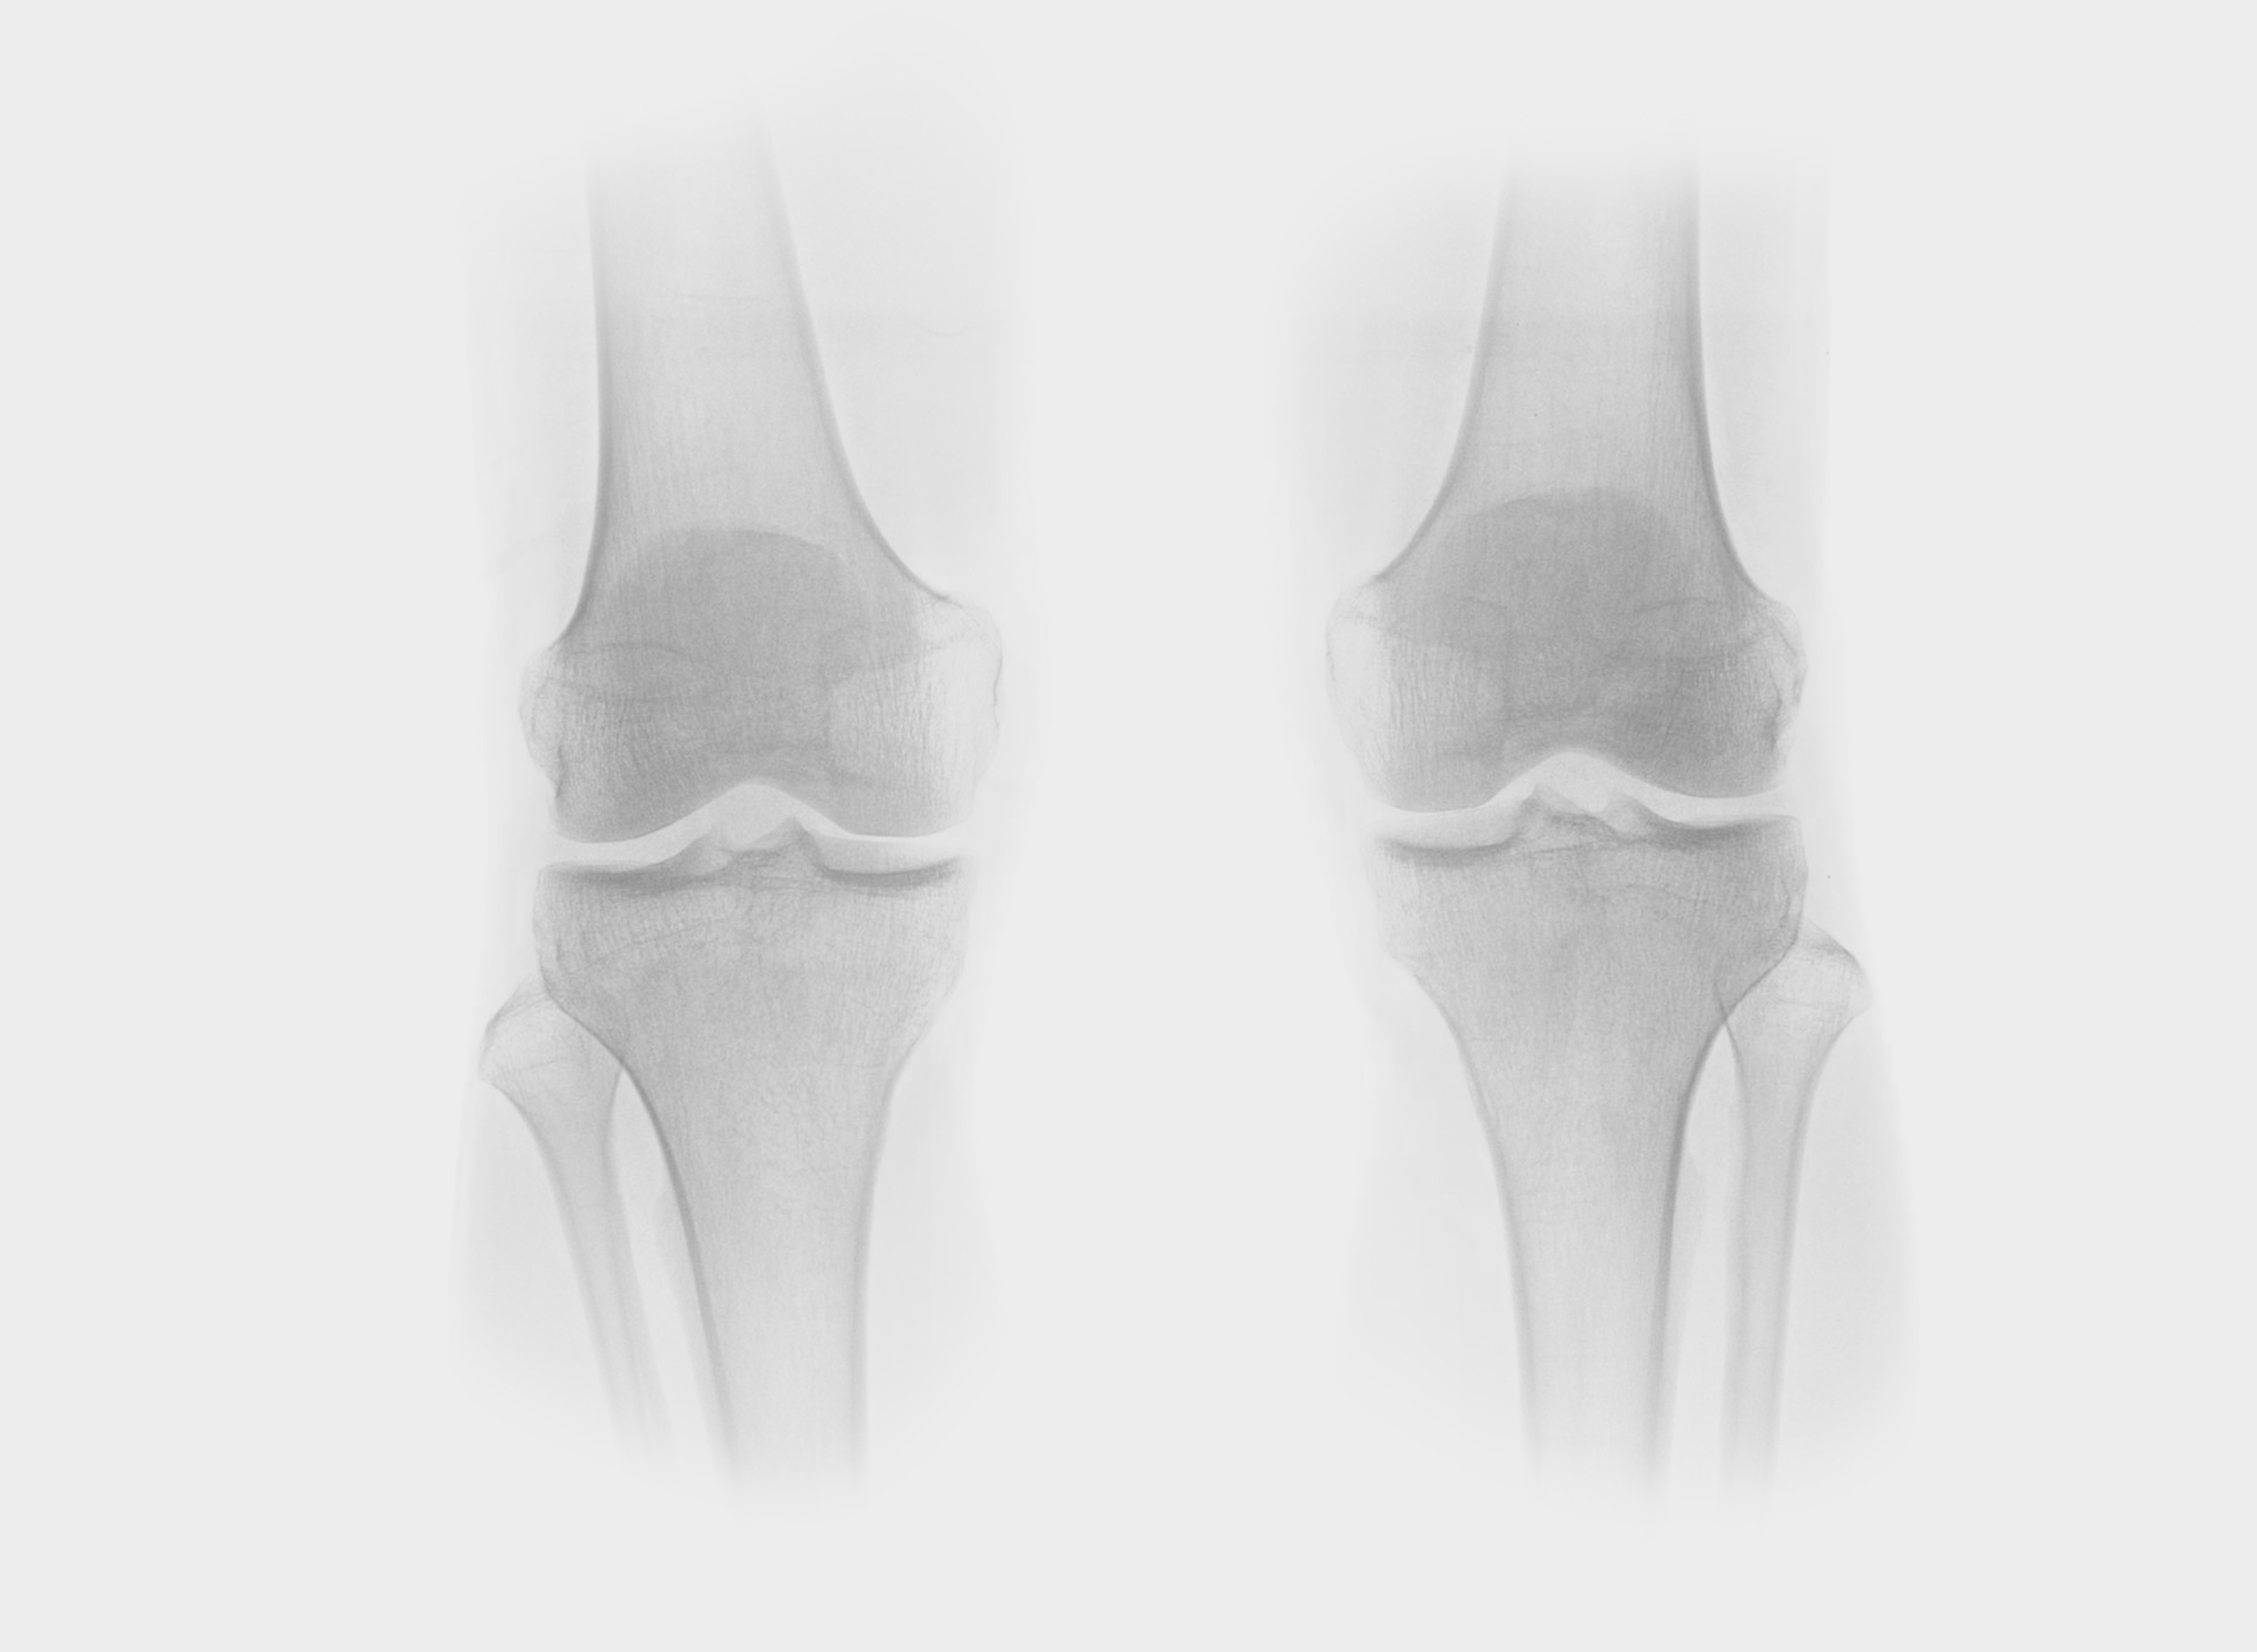

How it looks in practice

See how Carebot works in practice. Compare the image with AI and without AI.

Without Carebot

With Carebot